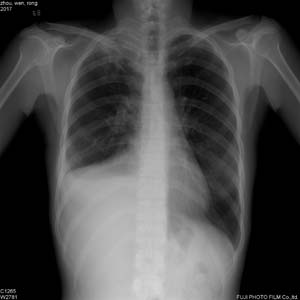

以下是引用dyqct在2006-11-25 21:53:00的发言:[br]右“膈”明显升高,外侧升高。右上肺野见多数条状高密度影,边界尚清楚。[br]考虑:1、右肺底积液;[br] 2、右上肺陈旧性肺结核;[br] 3、建议加照卧位或右侧卧位。